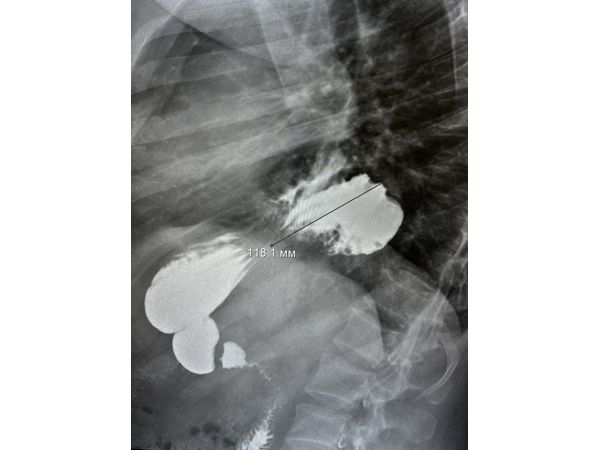

Вместо гастроскопии сделали рентгеноскопическое исследование пищевода, желудка и двенадцатиперстной кишки. По результатам удалось установить, что часть желудка расположена в грудной полости и зафиксирована в заднем средостении (между сердцем и позвоночником). Такое состояние соответствует фиксированной аксиальной кардио-фундальной грыже пищеводного отверстия диафрагмы.

Через месяц провели рентгенконтроль: грыжи не было, желудок расположен правильно (в брюшной полости). Гастроэзофагеального рефлюкса в положении Тренделенбурга (лёжа на спине, ступни немного выше головы) и стоя не выявлено.